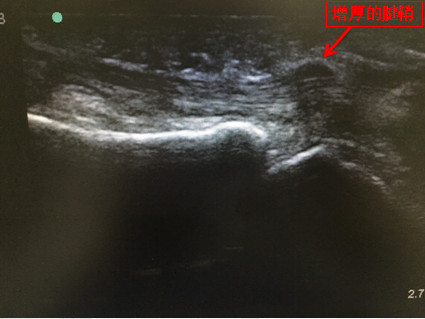

4.超聲引導(dǎo)下針刀松解術(shù):超聲引導(dǎo)就像“火眼睛睛”,可動態(tài)觀察肌腱的活動度,明確病變滑車的部位。在超聲引導(dǎo)下進行腱鞘下注射,在可視狀態(tài)下應(yīng)用針刀對增厚的滑車進行縱向松解。治療部位精準(zhǔn)、操作安全、有效、微創(chuàng)!

術(shù)中超聲影像

目前,超聲引導(dǎo)下針刀狹窄性腱鞘炎約500例,臨床有效率達(dá)95%以上。學(xué)成歸來的疼痛科醫(yī)生有了“火眼睛睛”,腱鞘炎頑疾病根無處遁形,手起刀落(微創(chuàng)針刀),靶點精準(zhǔn),集診斷診療于一身,治療效果良好,受到患者的一致好評!